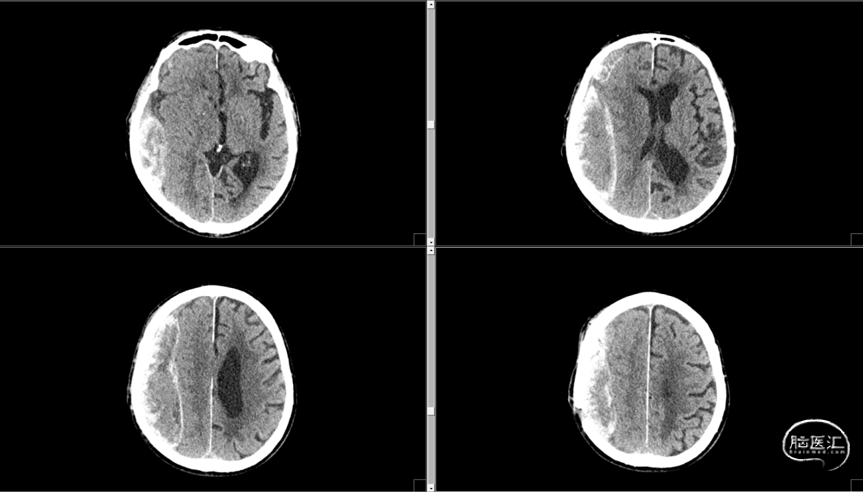

术后CT